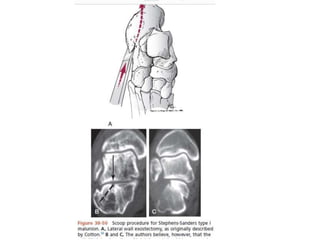

MIO - Fijación Clavos K y tornillo

AO Surgery Fundation Joseph Schatzker, Richard Buckley, Andrew Sands

Posición

Coughlin, Mann . Pie y tobillo, Cap 38 Fractura de calcaneo. Marban

Lateral extendida

Coughlin, Mann . Pie y tobillo, Cap 38 Fracturas de calcaneo. Marban

• Remover el hematoma fracturarlo

Reducción

Mac Rae , Fractura de calcáneo. cap. 39

Método

Eastwood

• Separa el frag

supero lateral

• Desimpacta

pared medial

• Reduce la

tuberosidad.

MIO - FijaciónClavos K y tornillo Indicaciones •Fractura intraarticular desplazada de tipo depresión articular. Individuo con malestar médico que impide la reducción total abierta Tipo de fractura simple (solo dos fragmentos) Pacientes mayores en los que la incisión ORIF grande puede tener un alto riesgo de complicaciones Contraindicaciones •Más de 3 días entre traumatismo e intervención quirúrgica. Depresión articulada tipo fractura Ventajas •La cirugía de incisión pequeña puede promover un mejor rango de movimiento en la rehabilitación temprana Menos posibilidades de complicación de la herida Oportunidad para la cirugía en pacientes médicos marginales (fumadores pesados, diabéticos) Desventajas •La reducción articular no se puede ver tan perfectamente AO Surgery Fundation Joseph Schatzker, Richard Buckley, Andrew Sands

• 35.

Posición Coughlin, Mann .Pie y tobillo, Cap 38 Fractura de calcaneo. Marban

• 36.

Lateral extendida AO SurgeryFundation Joseph Schatzker, Richard Buckley, Andrew Sands

• 37.

Coughlin, Mann .Pie y tobillo, Cap 38 Fracturas de calcaneo. Marban

• 38.

• Remover elhematoma fracturarlo

• 39.

AO Surgery FundationJoseph Schatzker, Richard Buckley, Andrew Sands

• 40.